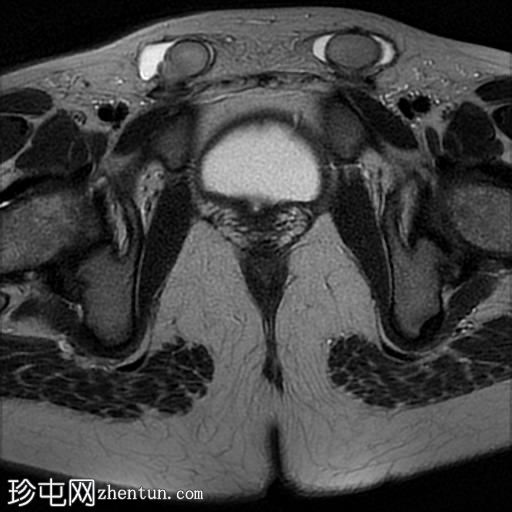

轴位

T2加权像

T1加权像

女性外生殖器

子宫、宫颈、阴道上2/3及卵巢缺失

双侧睾丸异位,沿腹股沟管清晰可见

MRI表现符合伴女性外生殖器的雄激素不敏感综合征(男性假两性畸形)。

受影响的个体基因型为男性,核型为46XY,但表型为女性(男性假两性畸形),且常伴有双侧隐睾。